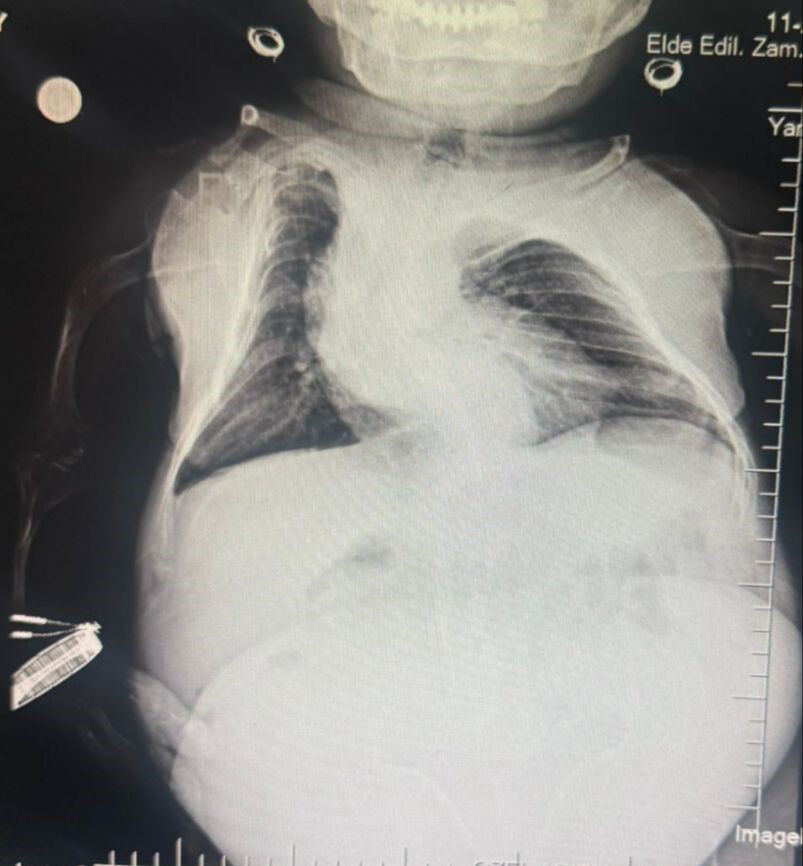

Karın ağrısı sandı, 3 kilogramlık kist çıktı - 1. Resim

Operasyona ilişkin açıklamalarda bulunan anestezi doktoru Mahmut Gül, "Hastamız 30 yaşında, 80 santimetre boyunda, 24 kilo ağırlığında bir kardeşimiz. Kendisinin yumurtalıklarında kist olduğu için ameliyat olması gerekti. Biz bu ameliyatta hastamıza önce büyük bir damar yolu açtık kasıktan. Çünkü damar yolunun çok önemi var. Ameliyat sırasında belinden uyuşturduk ve ameliyatı sorunsuz bir şekilde belden uyuşturmayla hastamız uyanık bir şekilde tamamladık. Hastadan 3 kilo kist çıktı. Öncesinde 24 kilo olan hastamız ameliyat sonrasında 21 kiloyla şifalı bir şekilde serviste yatıyor." dedi.